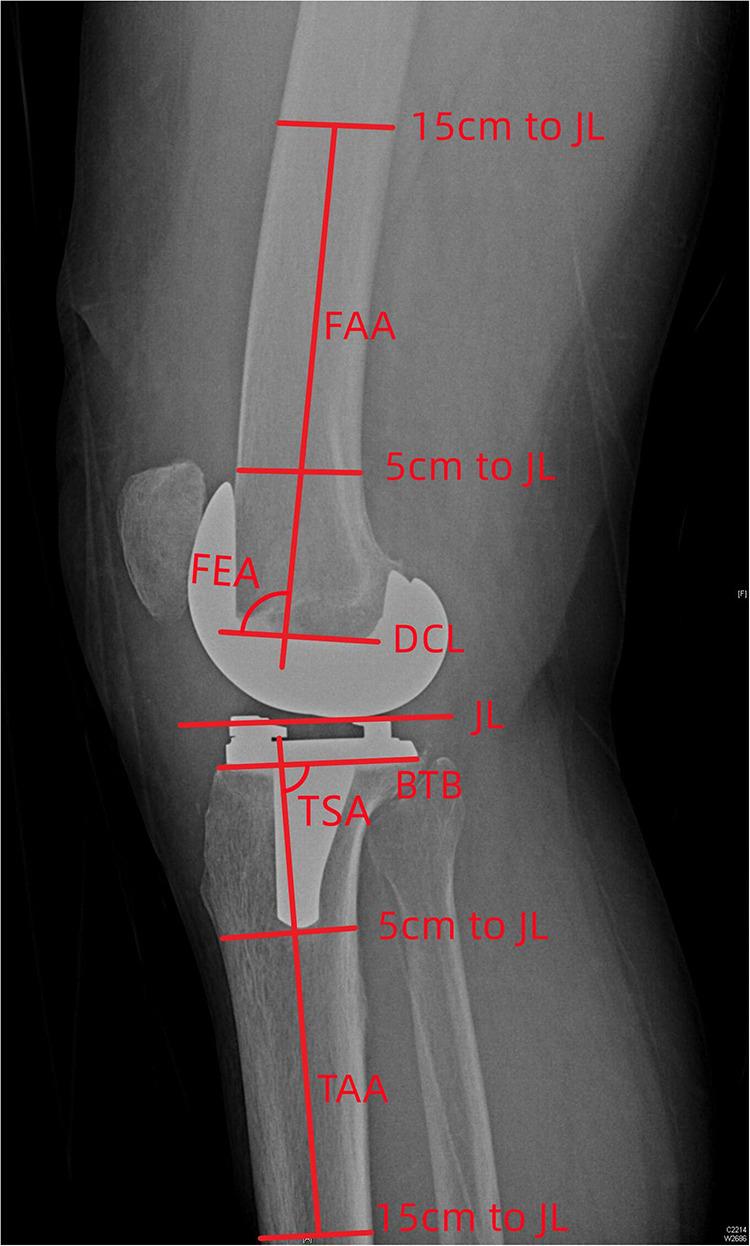

50 TKA patients from a regional hospital were enrolled in the study. The following component alignments were measured from radiological data acquired within 1 week after surgery: hip-knee-ankle angle (HKA), medial distal femoral angle (MDFA), medial proximal tibial angle (MPTA), femoral flexion-extension angle (FEA), tibial slope angle (TSA), femoral rotational angle (FRA) and tibial rotational angle (TRA). The Hospital for Special Surgery (HSS) knee scoring system was used to assess clinical outcomes after 1 year, with patients being divided into three groups (excellent, good and not good) according to the HSS scores. Difference analysis and linear correlation analysis were used for the statistical analysis.

方法